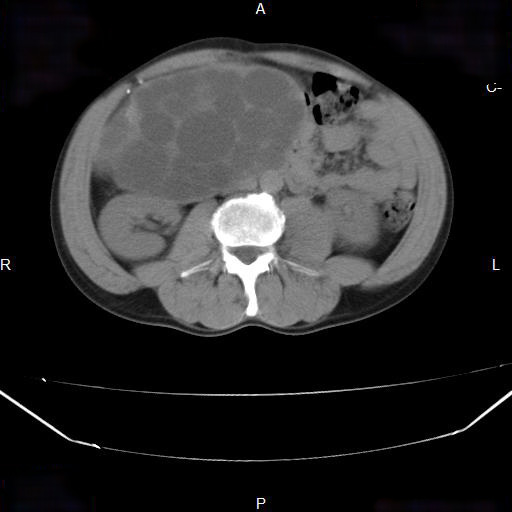

A soft tissue mass is noted in the fundus of the stomach, with lateral surface irregularity and gas locules on its surface. No exophytic/extra gastric component

No enlarged abdominal lymph nodes. No liver lesion within the limitation of the non contrast study.

Upper GI endoscopy revealed a lesser curvature mass. Pathologically proven GIST.

GISTs have a KIT receptor Tyrosine kinase